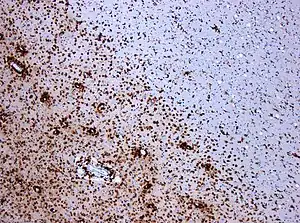

| CD68-stained tissue shows several macrophages in the area of a demyelinated lesion caused by MS. | |

Another cell population that is becoming increasingly implicated in MS are microglia. These cells are resident to & keep watch over the CNS, responding to pathogens by shifting between pro- & anti-inflammatory states. Microglia have been shown to be involved in the formation of MS lesions and have been shown to be involved in other diseases that primarily affect the CNS white matter. Although, because of their ability to switch between pro- & anti-inflammatory states, microglia have also been shown to be able to assist in remyelination & subsequent neuron repair.[15] As such, microglia are thought to be participating in both acute & chronic MS lesions, with 40% of phagocytic cells in early active MS lesions being proinflammatory microglia.[15]